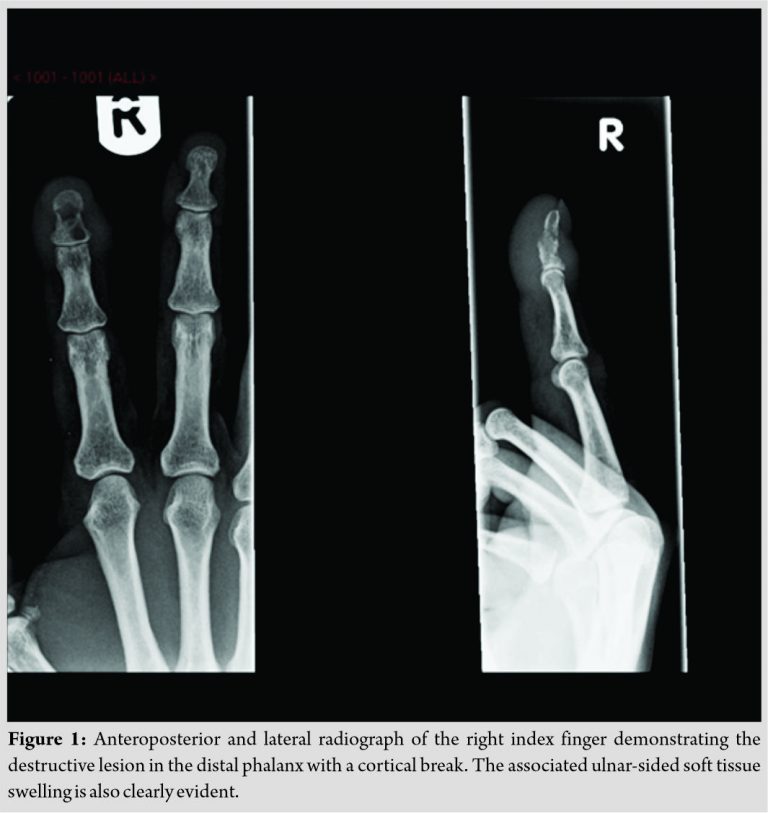

Radiological investigations showed a well-defined lesion in the distal phalanx with a fracture through the distal phalanx (Fig. 1). There was no periosteal reaction evident. Under the effect of a local anesthetic (Levobupivacaine + Lidocaine) and finger tourniquet, an incision was placed on the prominent aspect of the ulnar sided swelling over the distal phalanx. There was no pus encountered. A thorough debridement of the distal phalanx was performed (Fig. 2and 3) and samples were sent for culture and sensitivity. The patient was commenced on oral co-amoxiclav, pending sensitivity results. The finger was splinted for 4 weeks followed by gentle mobilization under the guidance of a hand therapist.